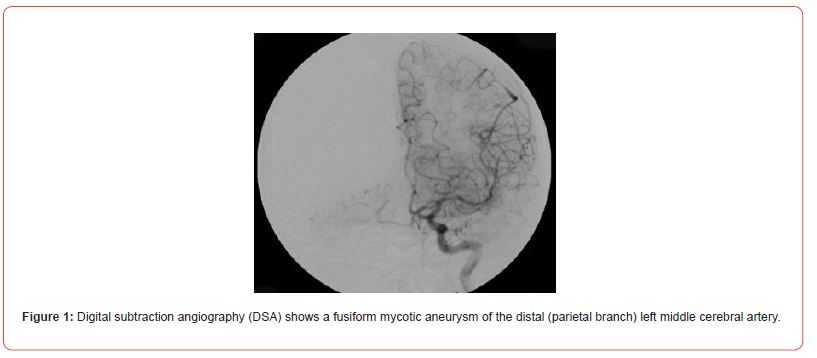

Infectious intracranial aneurysms, also called mycotic aneurysms, are localized arterial dilatations that arise as a consequence of septic emboli stemming from the complications of infective endocarditis and are reported to constitute a range of 0.5% to 6.5% of all aneurysmal cases [6]. The term “mycotic aneurysm” was first introduced by William Osler back in 1885 when he described where he described a man with multiple aortic mycotic aneurysms in a patient with valve vegetations, which resembled the appearance of a fishy fungus, It does not refer to fungal etiology, as the majority of infected aneurysms are caused by bacterial pathogens. Therefore, the correct term of these aneurysms can be an infected aneurysm. Infectious aortitis refers to vessel infection without aneurysmal dilation. An infected aneurysm develops in the setting of an antecedent systemic infections with bacteremia or through the direct local invasion of the vessel wall (e.g., IV drug users) in the pre-existing aneurysm or atheromatous plaques [7]. It was firstly by Osler described abnormal dilatation of the aortic arch vessel wall in a patient with subacute infective endocarditis [8]. Predominantly, these aneurysms tend to localize themselves along the peripheral branches of the middle cerebral artery (fg. 1) [5]. Infammatory processes trigger the influx of neutrophils that infiltrate the affected area. Subsequent stages encompass the breakdown of the arterial media and adventitia, along with the fragmentation of the internal elastic lamina. The weakened vessel wall, in combination with the pulsatile pressure in the vasculature, leads to aneurysm formation and consequential growth [9]. The mortality linked to the rupture of intracranial mycotic aneurysms, precipitating either subarachnoid hemorrhage or intracerebral hemorrhage, is documented to reach staggering levels, with reported rates as high as 80% [10] (Figure 1).